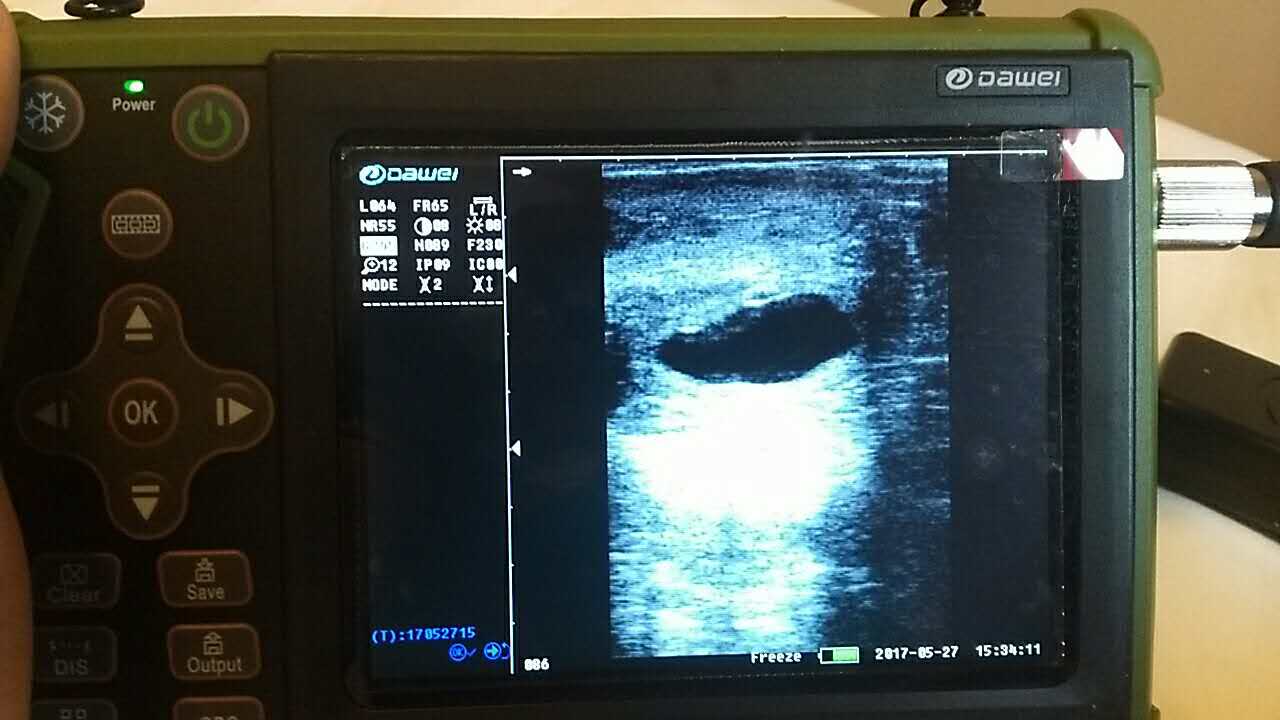

| 羊場(chǎng)母羊照B超辨受孕促增產(chǎn) |

養(yǎng)殖基地140只生產(chǎn)母羊集體接受了B超檢查,利用現(xiàn)代化技術(shù)方法,解決生產(chǎn)母羊繁育難題促進(jìn)畜牧業(yè)生產(chǎn)結(jié)構(gòu)的調(diào)整。 在檢查中,技術(shù)人員拿著B超儀器,給生產(chǎn)母羊做免費(fèi)受孕普查。用B超檢測(cè)母羊受孕情況,用這種方法給母羊做檢測(cè)可以準(zhǔn)確掌握母羊是否受孕、母羊生產(chǎn)周期。通過(guò)B超早期孕檢和生殖系統(tǒng)疾病診斷,可以清晰的觀測(cè)到生產(chǎn)的宮腔和胎兒的生產(chǎn)發(fā)育情況。除了幫助基地對(duì)問(wèn)題羊做出正確診斷,提出合理的治療方案,淘汰無(wú)治療價(jià)值的長(zhǎng)期空懷羊,還能提高受孕率,降低飼養(yǎng)成本,有效規(guī)避了假妊娠造成的經(jīng)濟(jì)損失。

以前傳統(tǒng)的養(yǎng)殖模式中,母羊懷孕全靠目測(cè),如果沒(méi)看出來(lái),做防疫或其他檢查時(shí)就會(huì)導(dǎo)致母羊流產(chǎn),一只羊錯(cuò)過(guò)一個(gè)受孕周期,平均損失就在500元左右。通過(guò)B超檢測(cè)可以提高產(chǎn)羔率,更加合理的區(qū)分受孕和不受孕母畜,對(duì)不同對(duì)象進(jìn)行科學(xué)合理的投入和管理,使養(yǎng)殖基地的生產(chǎn)母羊養(yǎng)殖效益最大化。

檢測(cè)懷孕 估測(cè)胎仔數(shù) 疾病診斷 胎兒活力鑒定 胎心搏動(dòng) 適用對(duì)象:適用于羊、豬、狗等動(dòng)物受孕診斷(集成6種常見(jiàn)動(dòng)物孕周測(cè)量數(shù)據(jù)包) 適用范圍:規(guī)模化豬場(chǎng),人工授精站,飼料/獸藥經(jīng)銷商及企業(yè),科研教學(xué)單位 |